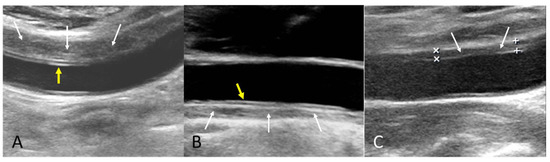

The B-mode findings of the nine CCAs revealed six typical double lumens with intimal flaps (Figure 2) and three intramural thrombi, which are also termed thrombosed false lumen (Figure 3). Supplementary Figures S1 and S2 contain the original ultrasound images. The “train-line” pattern was recognized in three of six intimal flaps and two of three intramural thrombi. The extracranial duplex sonography revealed a “train-line” pattern characterized by a thickened wall displaying hypoechoic properties, where the boundary was composed of closely placed parallel linear reflections. Patient No. 1 corresponds to Figure 2A; patient No. 2 corresponds to Figure 2B; patient No. 3 corresponds to Figure 2C,D; patient No. 4 corresponds to Figure 2E; and patient No. 5 corresponds to Figure 2F. Patient No. 6 corresponds to Figure 3A; patient No. 7 corresponds to Figure 3B; and patient No. 8 corresponds to Figure 3C. Interestingly, patient No. 5 had bilateral CCAD, but the train-line pattern was only on the right side. Figure 2C shows the right CCA with a double lumen and a clearly visible train-line pattern, and Figure 2D displays the left CCA, which also demonstrates a double lumen, but no train-line pattern is observed. Patient No. 8 presented with a hypoechoic intramural thrombus which resembled double lumens, but it was easy to distinguish under the color Doppler imaging.

Figure 3.

Intramural thrombus with train-line pattern (A,B) and without train-line pattern (C). The ultrasound image was obtained using a 4× magnification setting. Yellow arrows indicate the train line. White arrows indicate intramural thrombus. Symbols such as “×” and “+” were generated by the ultrasound machine and used by sonographers to mark ROIs.